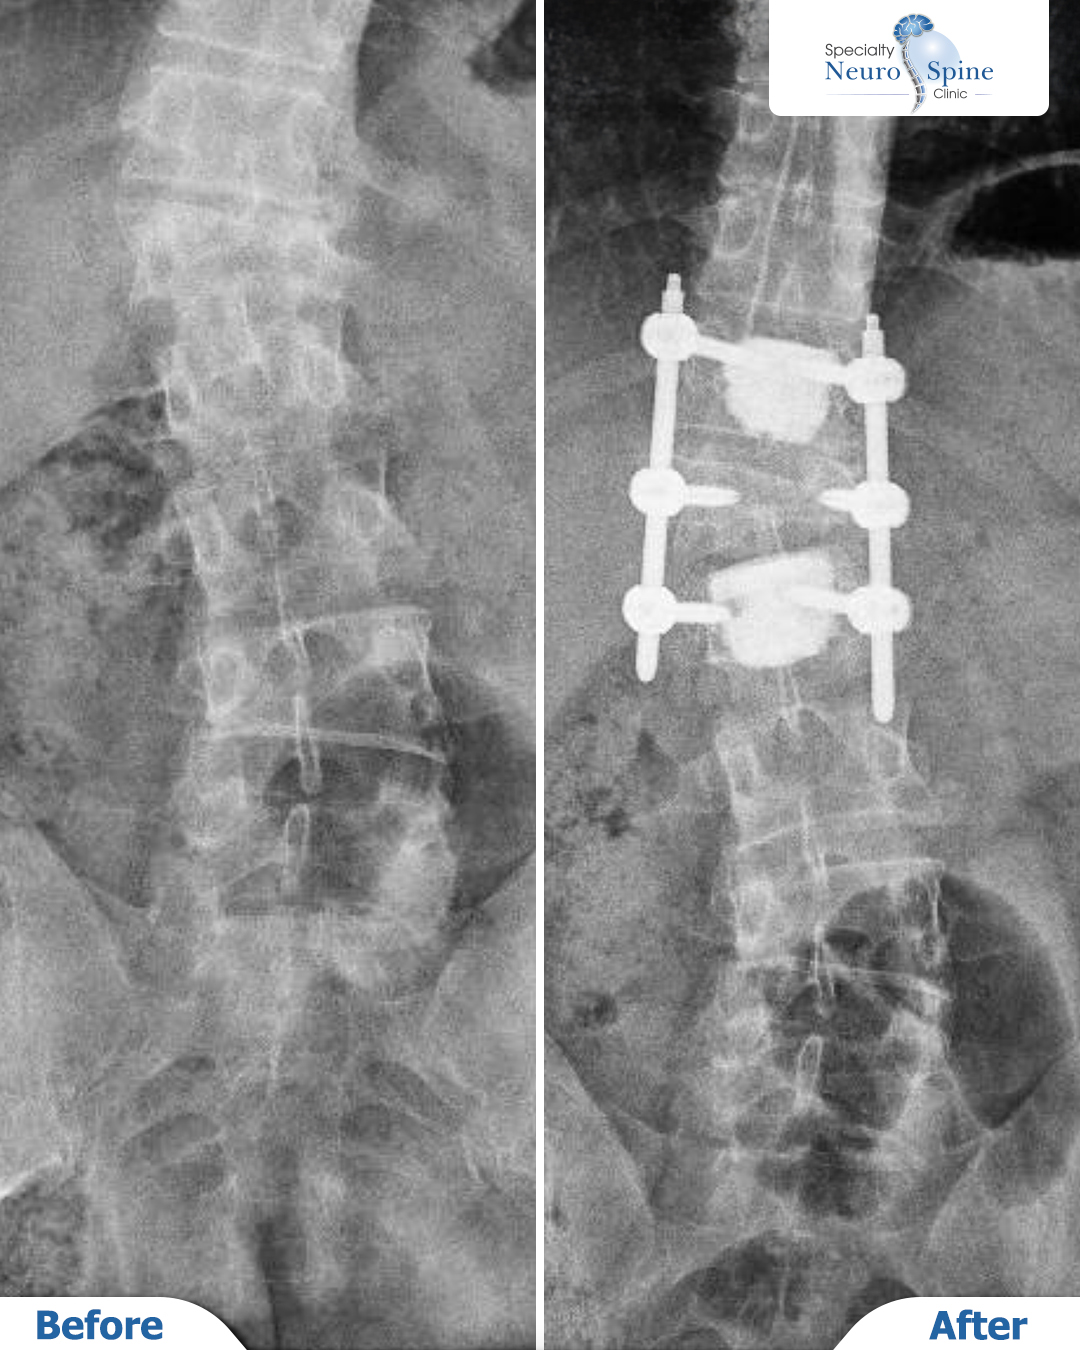

The X-ray images of our patient, Omar (41 years old from Iraq), illustrate the results following a spinal fixation procedure extending from the T12 to L2 vertebrae.

The surgery involved the use of screws and bone grafts to stabilize the vertebrae and repair the fracture caused by the accident. The images clearly demonstrate restored spinal stability after fixation, highlighting the success of this precise surgical intervention despite the challenges of osteoporosis.